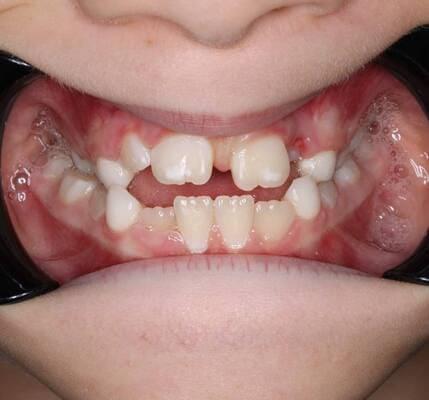

Один рік і два місяці вік дитини. Хтось скаже: «Що там тим зубам можна лікувати?!» Однак є ситуації, коли каріозний процес розвивається просто блискавично. Часто це пов’язано з порушеннями у формуванні твердих тканин ще внутрішньоутробно. А коли такі зубчики прорізуються, руйнування відбувається просто «на очах». Вісім із восьми зубів уражені, а 4 з них потребують часткового видалення пульпи («нерва»). На цьому етапі зуби вже починають турбувати і не зважаючи на юний вік дитини, зволікати не можна. Завдяки високій компетенції наших анестезіологів, які працюють з дітьми від самого народження і навіть з передчасно народженими, ми можемо проводити відповідне лікування в анестезіологічному забезпеченні за потреби навіть з першого зуба. Верхнім зубчикам, які сильно уражені, служити до 7-8 років, тому вони покриваються стандартними естетичними цирконієвими коронками, які дають максимальний результат по надійності, функції та естетиці. Година з половиною роботи і дитина може знову кусати без болю і дискомфорту. Важливо пам’ятати: для лікування зубів ніколи не буває “зарано”, це потрібно робити тоді, коли є відповідні показання